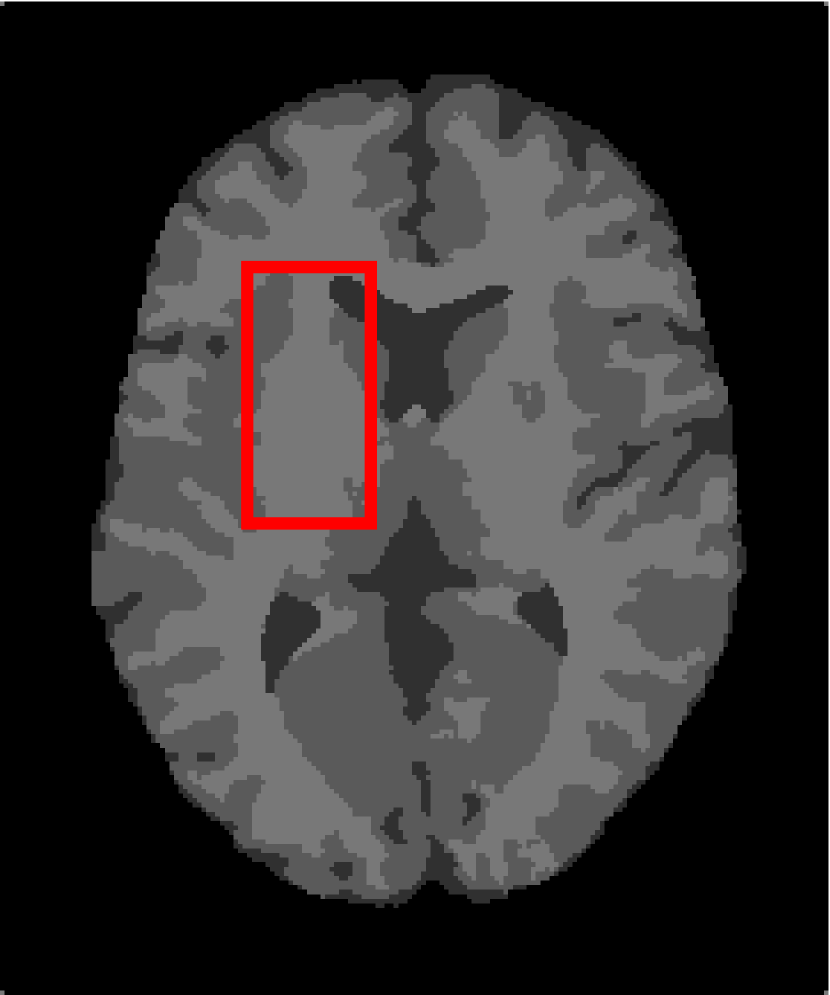

Next, we representatively segment five medical images from BrianWeb. They are represented as five slices in the axial plane with a sequence of 70, 80, 90, 100 and 110, which are generated by T1 modality with slice thickness of 1mm resolution, 9% noise and 20% intensity non-uniformity. Here, we set c=4𝑐4c=4 for all cases. The comparison between WRFCM and its peers are shown in Fig. 9 and Table II. The best values are in bold.

Figure 9: Segmentation results on five medical images. The parameter: ϕ=5.35italic-ϕ5.35\phi=5.35. From top to bottom: noisy images, ground truth, and results of FCM_S1, FCM_S2, FLICM, KWFLICM, FRFCM, WFCM, DSFCM_N, and WRFCM.

By a view of the marked red square in Fig. 9, we find that FCM_S1, FCM_S2, FLICM, KWFLICM and DSFCM_N are vulnerable to noise and intensity non-uniformity. They give rise to the change of topological shapes to some extent. Unlike them, FRFCM and WFCM achieve sufficient noise removal. However, they produce overly smooth contours. Compared with its seven peers, WRFCM can not only suppress noise adequately but also acquire accurate contours. Moreover, it yields the visual result closer to ground truth than its peers. As Table II shows, WRFCM obtains optimal SA, SDS and MCC results for all five medical images. As a conclusion, it outperforms its peers visually and quantitatively.